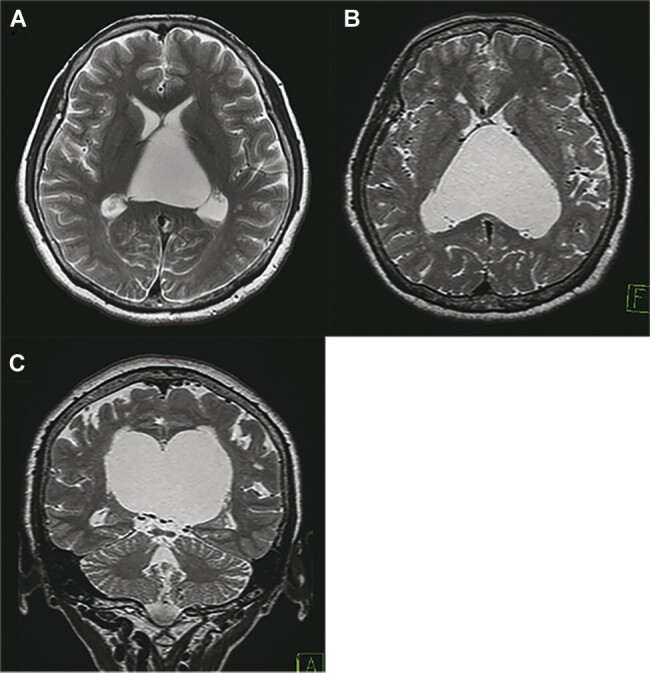

We report a patient with an arachnoid cyst in the velum interpositum (VI) and discuss the mechanism of the symptoms based on functional neuroanatomy. A 68-year-old woman presented with difficulty in doing housekeeping and with route-finding disorientation in known locations. Her performance intelligence quotient (PIQ) score was 68, significantly lower than her verbal intelligence quotient (IQ) of 103. Significantly low scores were obtained for the picture arrangement, picture completion, and symbol search tasks (4, 1, and 5, respectively) in the PIQ subtests. Her copies of the interlocking pentagons and cube designs were distorted, indicating visual-spatial construction apraxia. However, verbal IQ, working memory, urination control, ideational and ideomotor function, and dressing were intact. Magnetic resonance imaging revealed a cystic enlargement of the VI. Neuroendoscopic cyst fenestration to the lateral ventricles contributed to a decrease in the volume of the cyst. Postoperatively, her PIQ improved to 94. Her scores on the picture arrangement, picture completion, and symbol search tests increased to 7, 7, and 11 points, respectively. The pentagons and cube designs were copied correctly. An arachnoid cyst in VI is known to present with cognitive dysfunction. In our patient, symptoms were limited to the constructional apraxia and route-finding disorientation owing to the disturbance in the biparietal connections and posterior cingulate gyrus, respectively. The intramantle pressure gradient created by the characteristic cone-shaped cyst may have caused the selective dysfunctions. Namely, the impairment in the deep parietal region was more severe than on the frontal lobes or superficial parietal lobes.